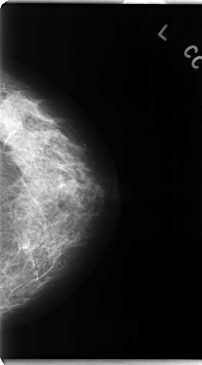

C_0162_1.LEFT_CC

LEFT_CC LINES 4736 PIXELS_PER_LINE 2624 BITS_PER_PIXEL 12 RESOLUTION 50 NON_OVERLAY